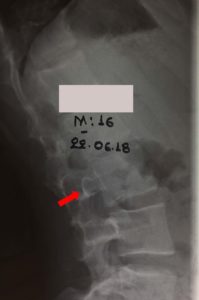

Τον Μάρτιο του 2015, σε ηλικία 13 χρόνων, έγινε έλεγχος της Οσφυϊκής Μοίρας της Σπονδυλικής Στήλης (ΟΜΣΣ) δια απλών ακτινογραφιών (Εικ.1-α,β,γ)

- α

- β

- γ

Εικόνα 1 α,β,γ

Προσθιοπίσθιες (α-β) ακτινογραφίες και πλάγια (γ) της ΟΜΣΣ : Δεν διαπιστώνεται η ύπαρξη παθολογικής εξεργασίας ή ανωμαλίας στους σπονδύλους της ΟΜΣΣ.